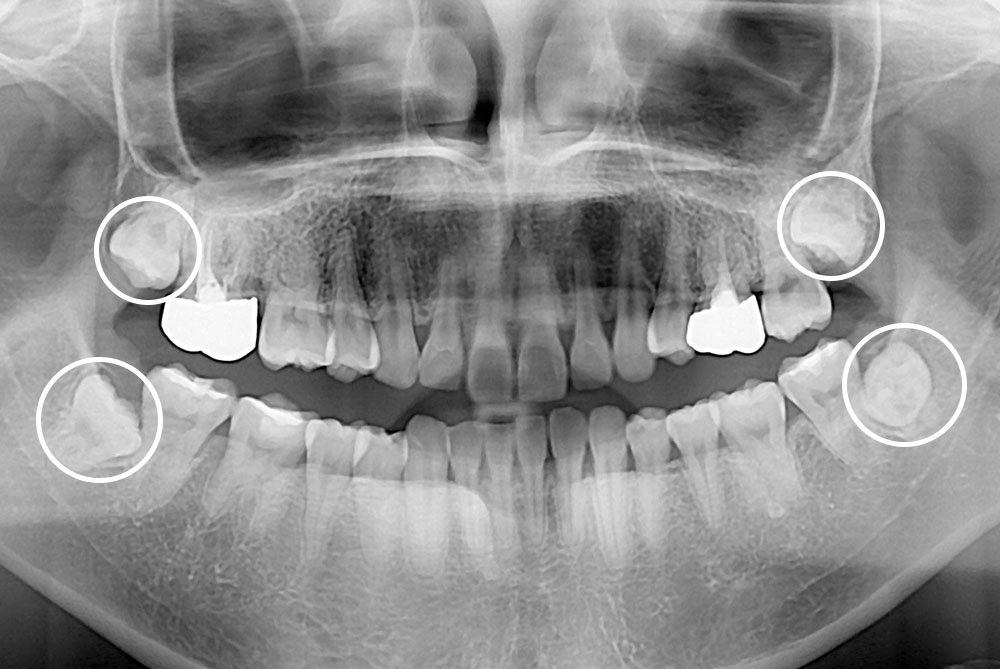

[사랑니] 매복 사랑니 발치

치료전 : 2018-02-13